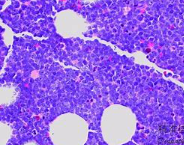

B淋巴细胞,也称为B细胞,是一种免疫系统中的重要细胞类型。作为脊椎动物免疫系统的一部分,B淋巴细胞在机体抵御病原体、产生抗体以及调节免疫应答等方面起着关键作用。

B淋巴细胞是一类由骨髓中的造血干细胞发育而来的淋巴细胞。它们主要存在于淋巴组织(如脾脏、淋巴结)和黏膜组织(如肠道和呼吸道)。B淋巴细胞具有特殊的受体,称为B细胞受体(BCR),它能够识别并结合病原体表面的抗原。

当B细胞受体与病原体抗原结合时,B细胞会被激活并开始分裂增殖。一部分活化的B细胞会转化为浆细胞,这些细胞能够产生大量的抗体,以中和和清除病原体。另一部分活化的B细胞会形成记忆B细胞,它们能够长期存活,并在再次遇到相同抗原时迅速启动免疫应答,以提供更快、更强的保护。

B淋巴细胞在免疫系统中的功能多样且重要,对于抵御感染、控制肿瘤生长以及自身免疫病的发生起着关键作用。研究B细胞的发育、激活机制以及其与其他免疫细胞之间的相互作用,有助于深入理解免疫系统的工作原理,并为免疫相关疾病的治疗和预防提供新的思路和方法。

5、参与疾病:B淋巴细胞在某些疾病中发挥着重要的作用。例如,在自身免疫疾病中,B细胞可能会产生自身抗体,攻击人体自身组织;在淋巴瘤等癌症中,B细胞可能会失控增殖,导致恶性肿瘤的形成。